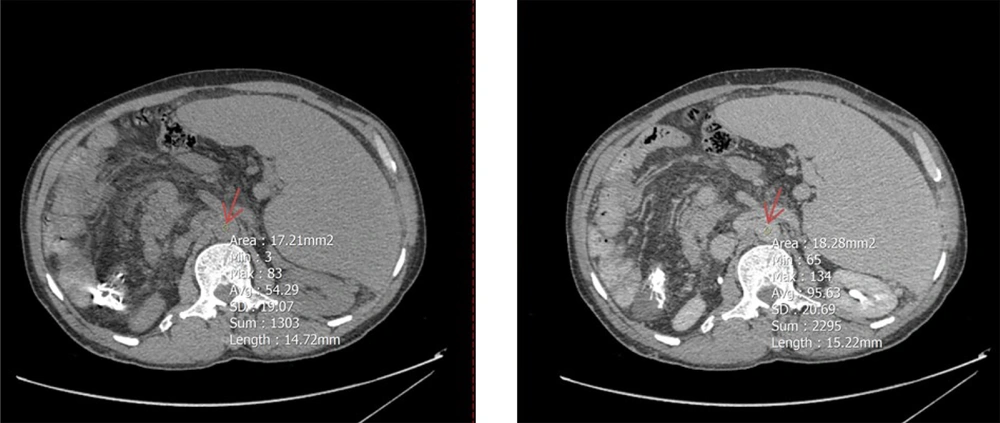

To determine mean Hounsfield units (HU) in both equilibrium and non-contrast phases, circular regions of interest (ROIs) were drawn as large as possible at specific anatomical landmarks. These included the right hepatic lobe at the level of the porta hepatis (Figure 2), the pancreas (head, body, and tail; averaged HU from the three segments was used to represent the whole organ) (Figure 3), and the spleen at its widest cross-sectional area, excluding vessels and focal lesions (Figure 2). An additional ROI with a 15-mm diameter was placed in the abdominal aorta at the level of the renal artery origin (Figure 4).

A circular region of interest (ROI, indicated by red arrows) was placed as large as possible on axial computed tomography (CT) images in both noncontrast (left) and equilibrium (right) phases. The upper panels show ROI placement in the right hepatic lobe at the level of the porta hepatis, while the lower panels demonstrate ROI positioning within the spleen at its maximum cross-sectional area, excluding visible vessels and focal lesions.